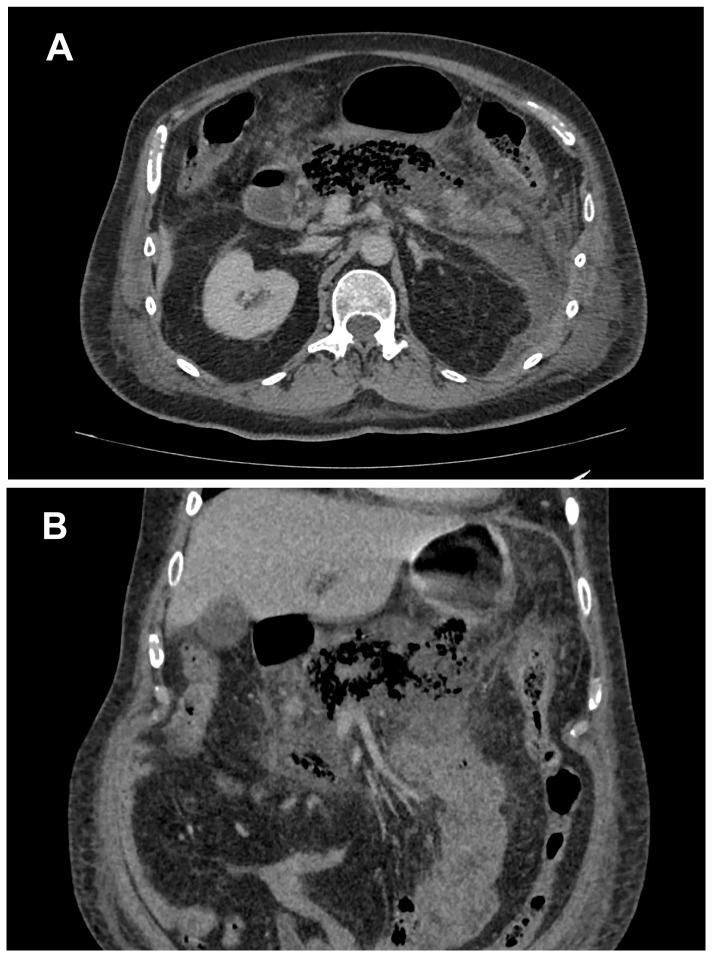

Emphysematous Pancreatitis as a Life-Threatening Condition: A Case Report and Review of the Literature.

Emphysematous pancreatitis represents the presence of gas within or around the pancreas on the ground of necrotizing pancreatitis due to superinfection with gas-forming bacteria. This entity is diagnosed on clinical grounds and on the basis of radiologic findings. Computed tomography is the preferred imaging modality used to detect this life-threating condition. The management of emphysematous pancreatitis consists of conservative measures, image-guided percutaneous catheter drainage or endoscopic therapy, and surgical intervention, which is delayed as long as possible and undertaken only in patients who continue to deteriorate despite conservative management. Due to its high mortality rate, early and prompt recognition and treatment of emphysematous pancreatitis are crucial and require individualized treatment with the involvement of a multidisciplinary team. Here, we present a case of emphysematous pancreatitis as an unusual occurrence and discuss disease features and treatment options in order to facilitate diagnostics and therapy.